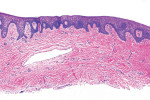

The histologic evaluation showed collagen that aligned horizontally, in a mostly parallel nature, to the superficial epithelium in both the ungrafted (Figure 10 and Figure 11) and grafted (Figure 12 through Figure 15) biopsy sites. In the grafted specimens, a clear demarcation at the interface of the native tissue and the implanted tissue was present. The implanted tissue, which was characterized by dense bands of disorganized collagen matrix, appeared well incorporated and without inflammatory cells. The Verhoeff's stain demonstrated the presence of numerous darkly stained elastin fibers in the implanted tissue that were inconspicuous in the native tissue.

The H&E and Verhoeff's stains allowed the collagen architecture of the native tissue to be clearly distinguished from that of the implanted tissue. The superficial native tissue exhibited collagen fibers that aligned parallel to each other and the epithelium, whereas the implanted tissue exhibited collagen fibers that appeared disordered. The implanted tissue, however, was markedly thicker than the overlying native tissue. Verhoeff's stain, which stains elastin fibers, has been used to identify implanted ADMs in grafted GRD sites.1,4,15 In this case, the abundant darkly stained elastin fibers in the grafted specimen indicate that the hydrated ADM was incorporated and not absorbed or exfoliated. The absence of observable inflammatory cells indicated that the implanted hydrated ADM was immunologically inert.